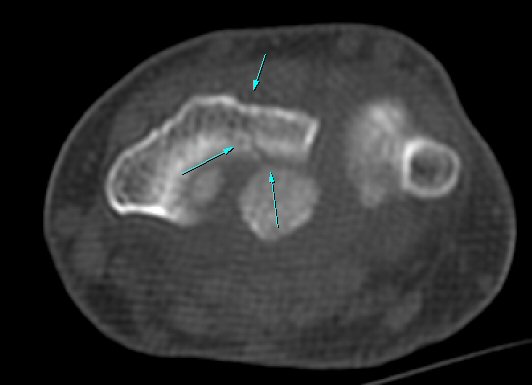

ÄÄÇ»ÅÍ ÃÔ¿µ: ¿ä°ñ ¿äÃø ¸»´Ü °ñÀý(÷ºÎ ÆÄÀÏ)